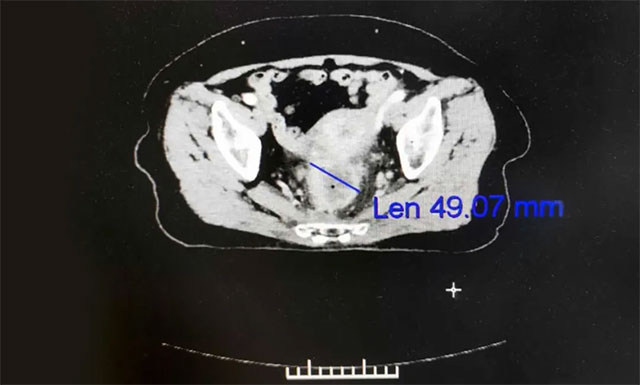

▲ 患者直腸癌再次復發(fā),病情嚴重

經(jīng)過復查,發(fā)現(xiàn)劉女士直腸局部腸壁不規(guī)則增厚,考慮仍有腫瘤活性,伴直腸周圍、左髂血管旁及腹膜后大血管多發(fā)淋巴結(jié)轉(zhuǎn)移,腹部造瘺術(shù)后改變,右半結(jié)腸炎性改變。之后,為求進一步放射治療,劉女士在家人的陪伴下于7月6日慕名就診于上海藍十字腦科醫(yī)院。

▲ 放療后患者病灶縮小,病癥逐漸緩解